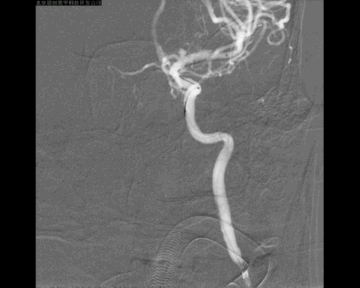

单弯导管在血管内呈螺旋状前进,因此微导管的塑形需要考虑到其在血管内螺旋前进的因素